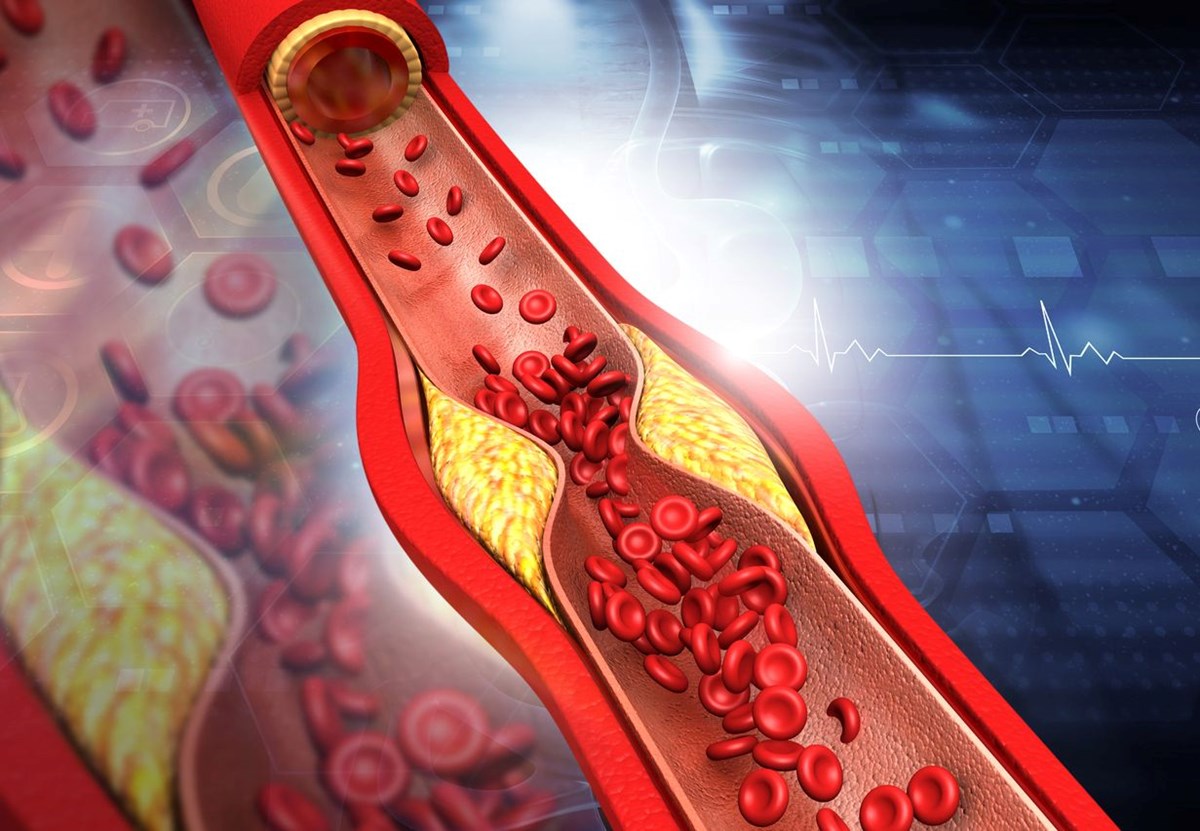

Kalp rahatsızlıkları riski her geçen gün artıyor ve buna en çok katkıda bulunan etkenlerden biri, atardamarlarda yoğun plak birikimiyle karakterize bir rahatsızlık. Bu plak, kötü kolesterol, yağ asitleri ve hücrelerden gelen atık maddelerden oluşur ve sonunda kan akışını yavaşlatarak atardamarları tamamen tıkar.

Yerleşik atardamar hastalıklarını tedavi etmek için bazen ilaçlar ve cerrahi müdahaleler gerekse de, doğal ve yaşam tarzına dayalı yöntemlerin plak birikimini tersine çevirebileceği giderek daha fazla gösteriliyor. Sağlıklı bir beslenmenin atardamarları temiz ve birikintilerden arındırılmış tutabileceği unutulmamalıdır, ancak plak oluşumunu tersine çevirebileceğini kanıtlayacak destekleyici bir kanıt yoktur. İşte atardamarları temizlemeye ve uzun vadeli kardiyovasküler sağlığı korumaya yardımcı olacak beş doğal ve etkili yöntem.

Sağlıklı kilo, kalp sağlığının sırrıdır . Özellikle göbek çevresindeki fazla vücut yağı, genellikle ateroskleroz ve kalp hastalıkları riskinin daha yüksek olduğunun bir göstergesidir. Vücut ağırlığının sadece %5-10 oranında azaltılması, fiziksel egzersizle birleştirildiğinde kan basıncı ve kolesterol seviyelerinde önemli bir iyileşme sağlayabilir ve hatta insülin duyarlılığını artırabilir.

Damar sağlığını iyileştirmenin en etkili yollarından biri yediklerimizdir. Tam gıdalardan oluşan doğal olarak yüksek lifli bir beslenme, iltihabı azaltabilir, LDL'yi düşürebilir ve genel damar fonksiyonunu iyileştirebilir. Yulaf ve esmer pirinç gibi tam tahıllar, kolesterolün bağlanmasına ve kandan atılmasına yardımcı olan çözünür lif sağlar. Beslenmeye sağlıklı yağlar eklemek, vücuttaki kolesterol dengesini iyileştirebilir. Öte yandan, aşırı miktarda işlenmiş gıda trans yağ bakımından zengindir, ilave şekerler ve rafine karbonhidratlar, arteriyel plak oluşumunu ve iltihabı hızlandırdığı tespit edildiğinden kaçınılmalıdır.Bu makale sadece genel bilgi verme amacıyla yazılmıştır ve doktor tavsiyesi olarak ele alınmaması gerekir. Makalenin içeriğinden yola çıkarak okurun kendi başına koyduğu teşhislerden ntv.com.tr sorumlu değildir. Sağlığınızla ilgili herhangi bir endişeniz varsa doktorunuza danışın.